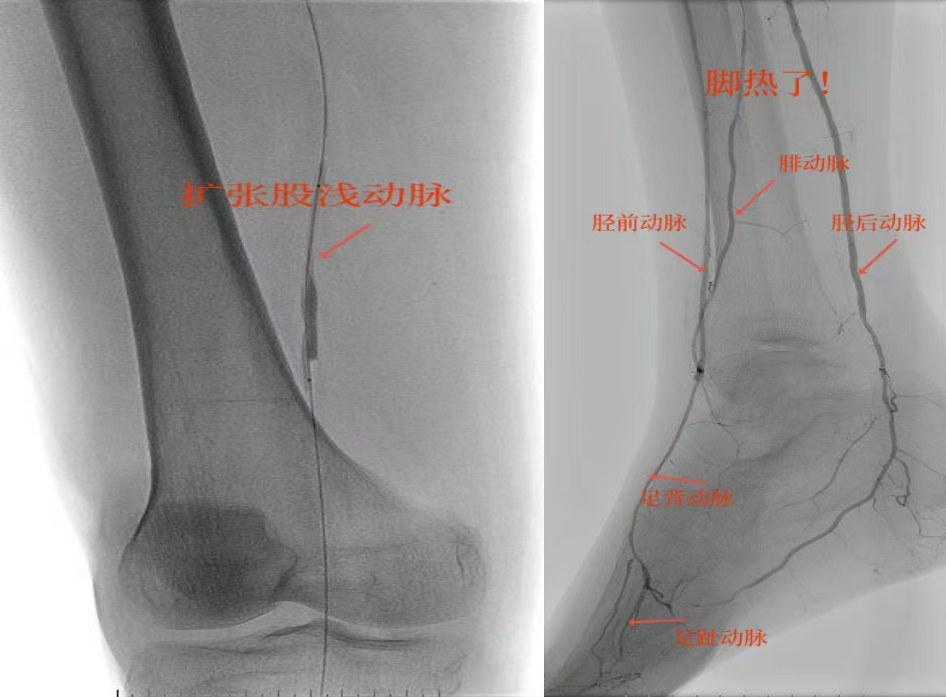

78岁男性患者,糖尿病合并高血压、脑梗塞,右足持续疼痛伴冰凉发绀3个月。入院CTA显示其右侧股浅动脉全程闭塞,膝下三支动脉均闭塞。医疗团队在局部麻醉下,再次巧妙应用“逆向开通技术”,经胫后动脉——足底弓逆向开通足背动脉及胫前动脉。术后患者右足皮温即刻回升,疼痛消失。术后结合中药外治(换药、熏洗、去腐生肌膏外敷)加速创面愈合,患者已顺利出院。

影像检查:CTA显示右侧股浅动脉全程闭塞,膝下三支动脉(胫前、胫后、腓动脉)完全闭塞。